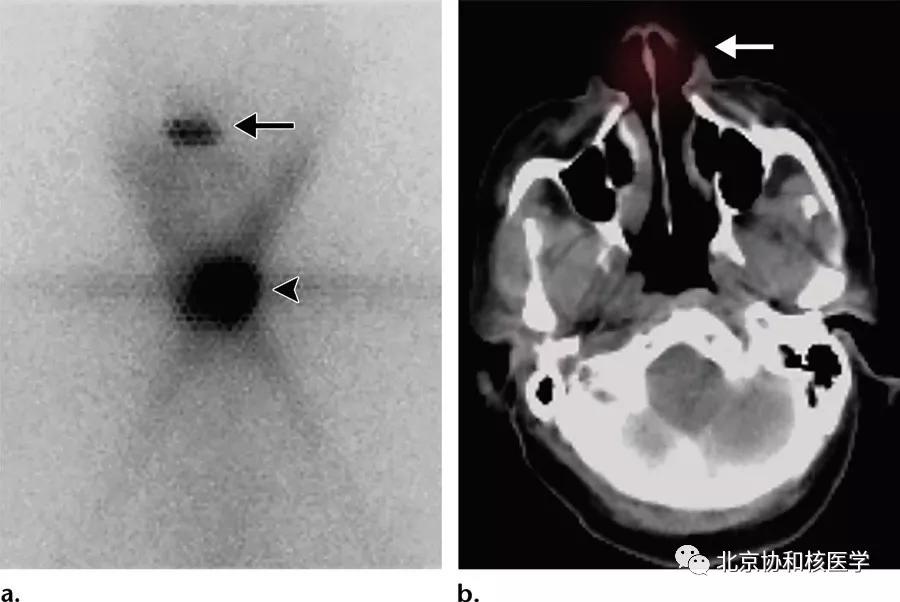

鼻腔脓肿所致碘摄取,其下方可见颈部残余甲状腺:

鼻腔息肉所致碘摄取,同时可见颈部残余甲状腺组织:

72岁男性,甲状腺全切术后(乳头状癌),碘131治疗后碘扫见鼻腔分泌物所致摄取: